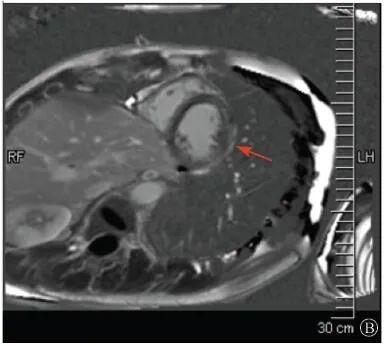

案例介紹:患者男性,20歲,因為"胸痛4個月,加重1月余"于2019年7月10日入院?;颊?019年4月無明顯誘因出現(xiàn)心前區(qū)隱痛,VAS 3分,無放射,無胸悶、憋氣、活動后氣短,每月發(fā)作1~2次,未在意。同年5月體檢發(fā)現(xiàn),肌酸激酶(CK)2928 U/L、肌酸激酶MB質(zhì)量(CK-MB)46 U/L、心肌肌鈣蛋白I(cTnI)0.055 ng/ml。6月初,患者"感冒"后出現(xiàn)心前區(qū)疼痛加重,為過電樣疼痛,VAS 5分,無放射,持續(xù)約30~60 min可好轉(zhuǎn),胸痛每周約發(fā)作2次,否認呼吸困難、胸悶、心悸,否認活動耐量下降。6月8日,患者就診于外院查血生化:CK 1 215→1433 U/L,CK-MB 47 U/L,cTnI 30.17→31.79 ng/L;血脂(-);抗核抗體譜(-);超聲心動圖:左室增大,左室舒張末內(nèi)徑57 mm,左室射血分數(shù)39%,輕度二尖瓣關(guān)閉不全;磁共振心肌灌注延遲動態(tài)成像(圖1):左室稍增大,收縮功能稍減低;基底部至心尖部左室下壁及側(cè)壁、心尖部左室前壁心外膜下心肌纖維化,考慮非缺血性心肌病;肌電圖:肌源性損害(偏慢性)。診斷"多發(fā)性肌炎、心肌損傷",予患者倍他樂克緩釋片23.75 mg/d、培哚普利0.5 mg/d、螺內(nèi)酯20 mg/d口服,患者未再出現(xiàn)心前區(qū)疼痛,但步行1 km左右會出現(xiàn)氣短、乏力。為進一步明確心力衰竭病因收入我院?;颊呱细咧衅鸪霈F(xiàn)體育課等劇烈活動后雙下肢明顯乏力,不能耐受1 km長跑類運動,日常體力活動不受影響,否認肌肉酸痛等不適。此次發(fā)病以來,一般情況尚可,否認尿量減少,體重無明顯變化。既往史:否認高血壓、冠心病、糖尿病病史。個人史:否認特殊毒物藥物接觸史,無煙酒嗜好。婚育史、家族史:未婚未育,否認家族類似病史,否認遺傳病史。入院查體:脈搏69次/min,血壓112/70 mmHg,指氧(自然狀態(tài))98%,體質(zhì)指數(shù)21.1 kg/m2;無皮疹;雙肺呼吸音清;心律齊,未聞及雜音;肝脾不大;雙側(cè)腓腸肌肥大,肌肉無壓痛;四肢肌力Ⅴ級、肌張力正常。雙下肢不腫。輔助檢查:入室床旁超聲心動圖提示左室壁運動普遍減低,心尖部、左室下后壁為著,肌小梁增多。

左室壁較廣泛心外膜下延遲強化,可見左室下后壁肌小梁增多(箭頭所示)

圖1 患者外院磁共振心肌灌注延遲動態(tài)成像